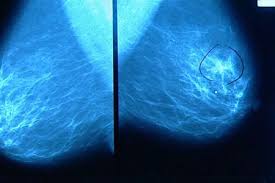

Portugal: Cancro da Mama: A importância do diagnóstico precoce

De modo a assinalar o Dia Nacional de Prevenção do Cancro da Mama, que se comemora a 30 de Outubro, o hospitalcuf infante santo recomenda o auto-exame mamário a todas as mulheres a partir dos 20 anos e a primeira mamografia por volta dos 40 anos.

Como não há maneira de evitar o cancro da mama, é fundamental diagnosticar o mais cedo possível, para que as opções de tratamento sejam as menos agressivas. “Actualmente o melhor exame de diagnóstico precoce é a realização periódica de uma mamografia e da ecografia mamária. Regra geral, esta vigilância deve ser iniciada a partir dos 40 anos, efectuando o exame de dois em dois anos até aos 50 anos, anualmente até aos 65 anos e de dois em dois anos a partir dessa idade”, refere Luís Mestre, coordenador da unidade de Senologia do hospitalcuf infante santo.